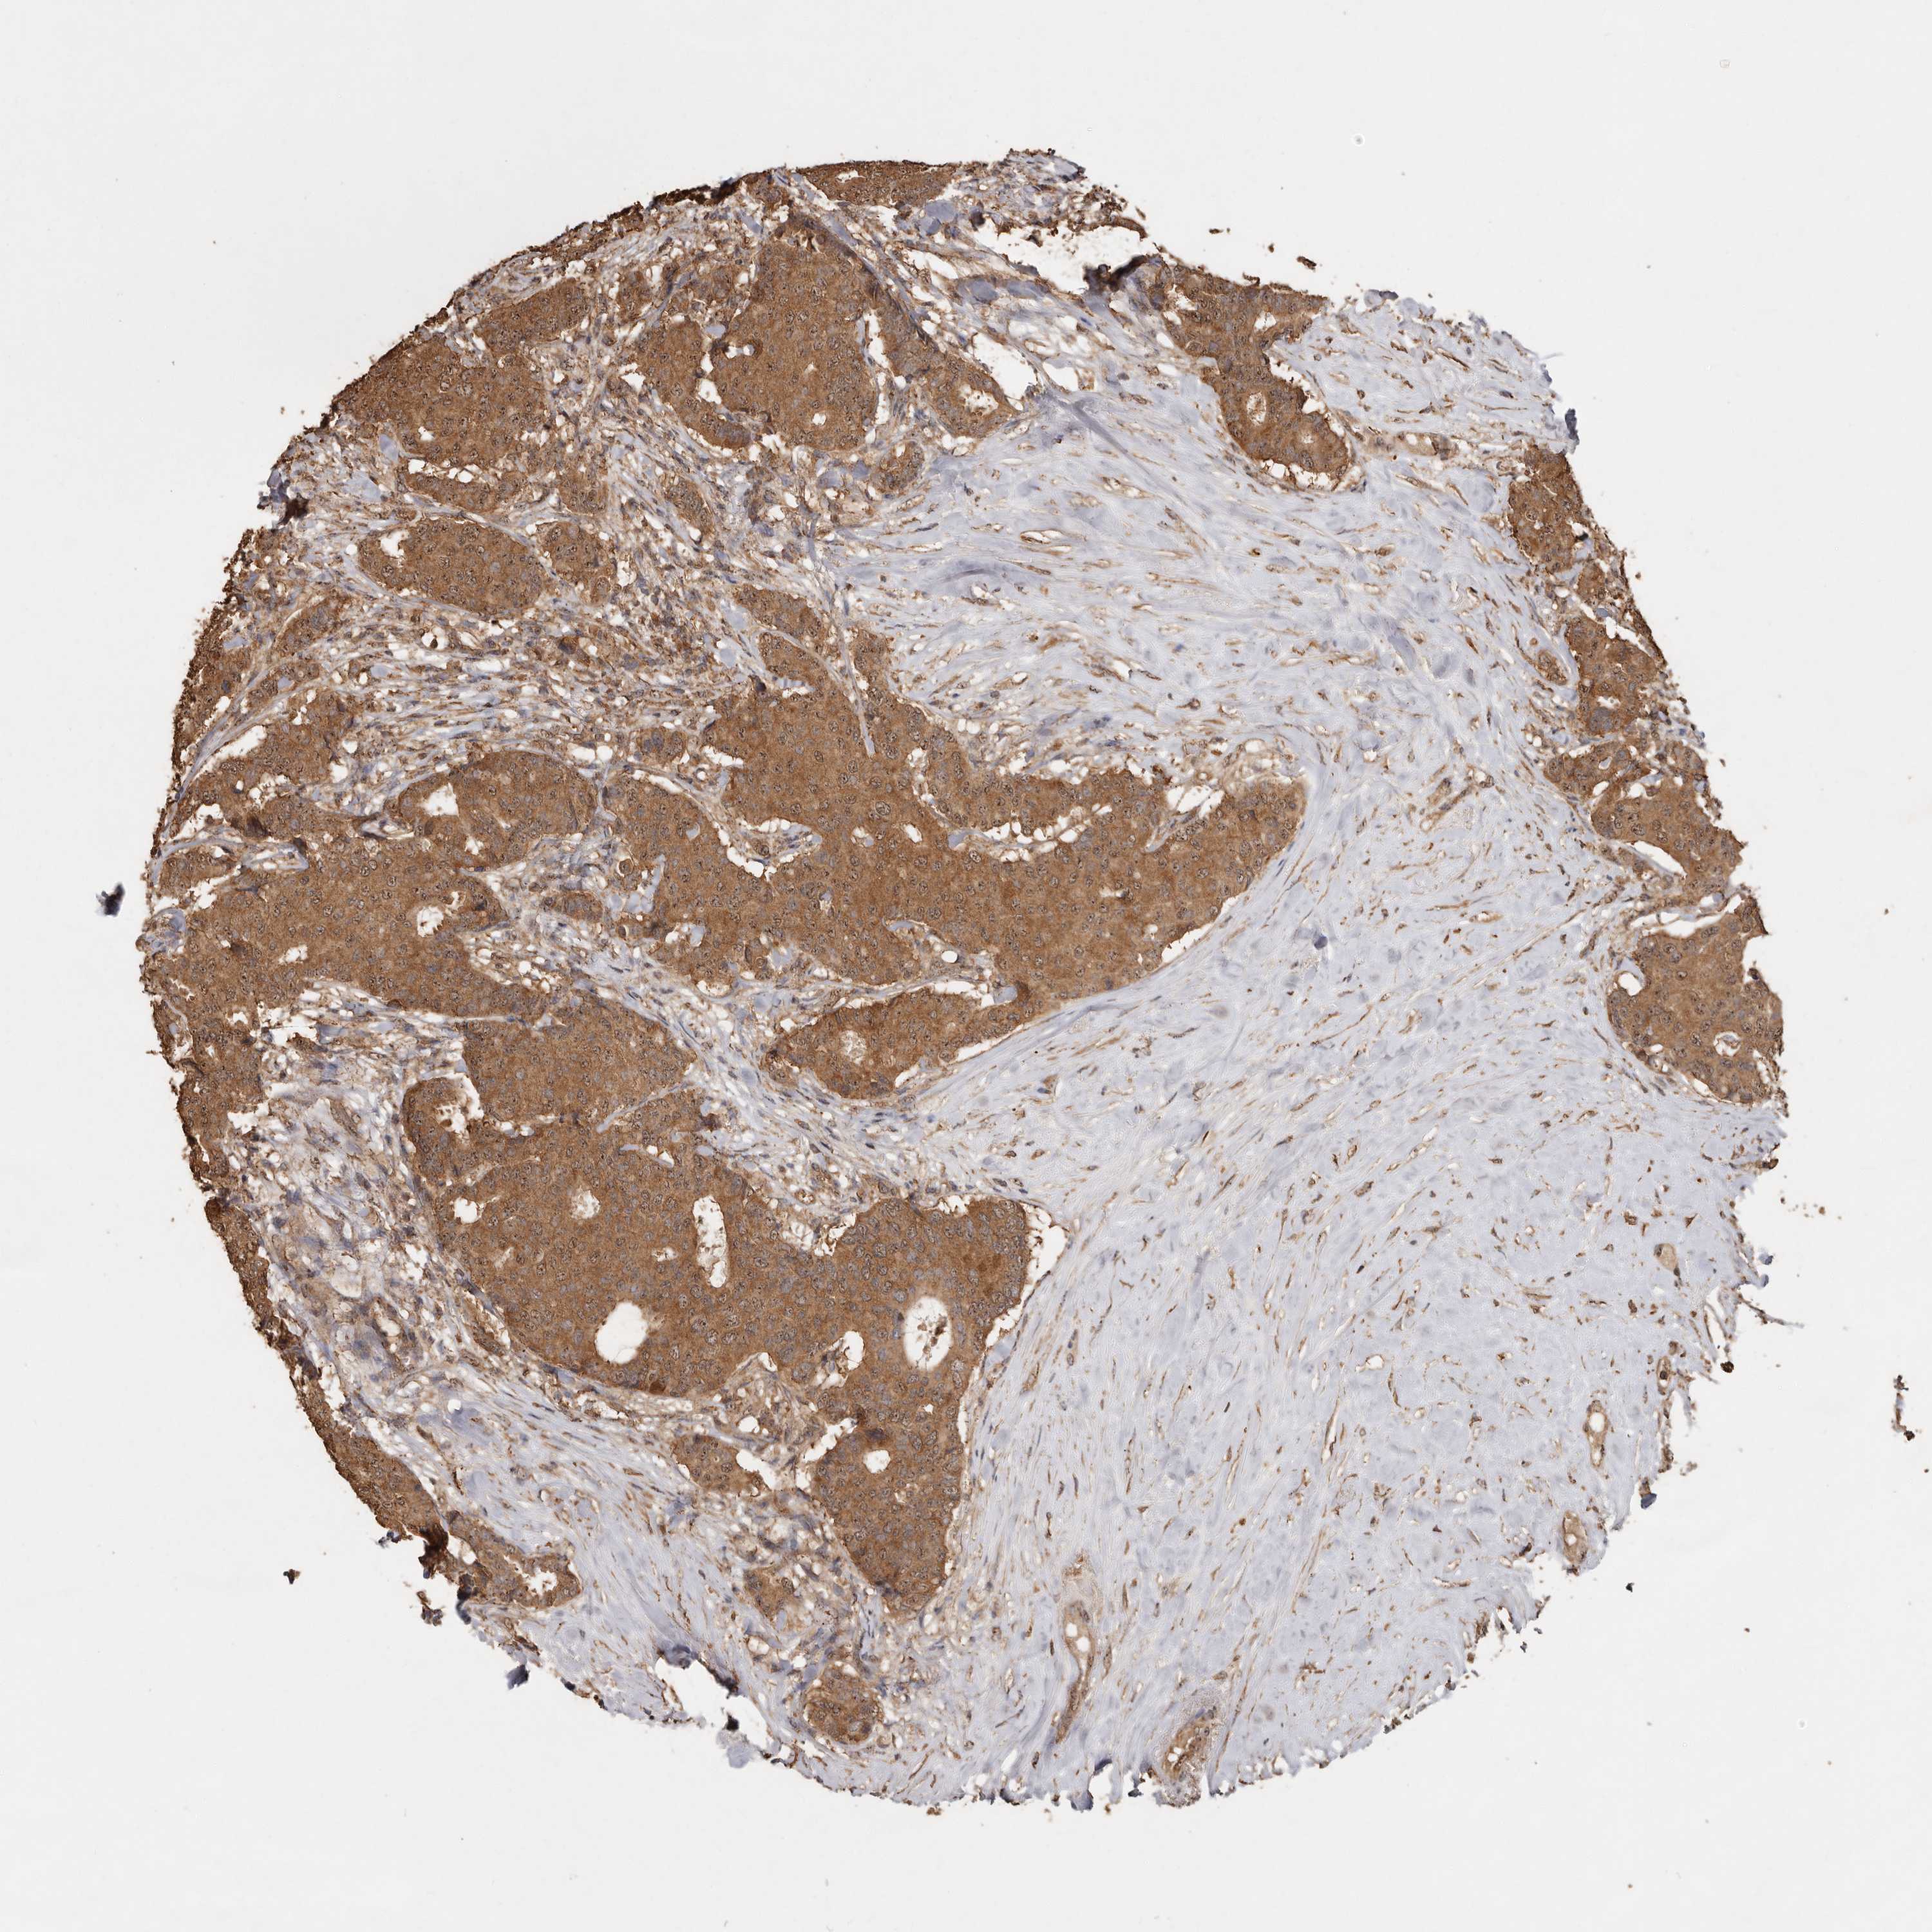

CANCER BREAST CANCER Show tissue menu

BRCA TCGA BRCA VALIDATION PROTEIN EXPRESSION